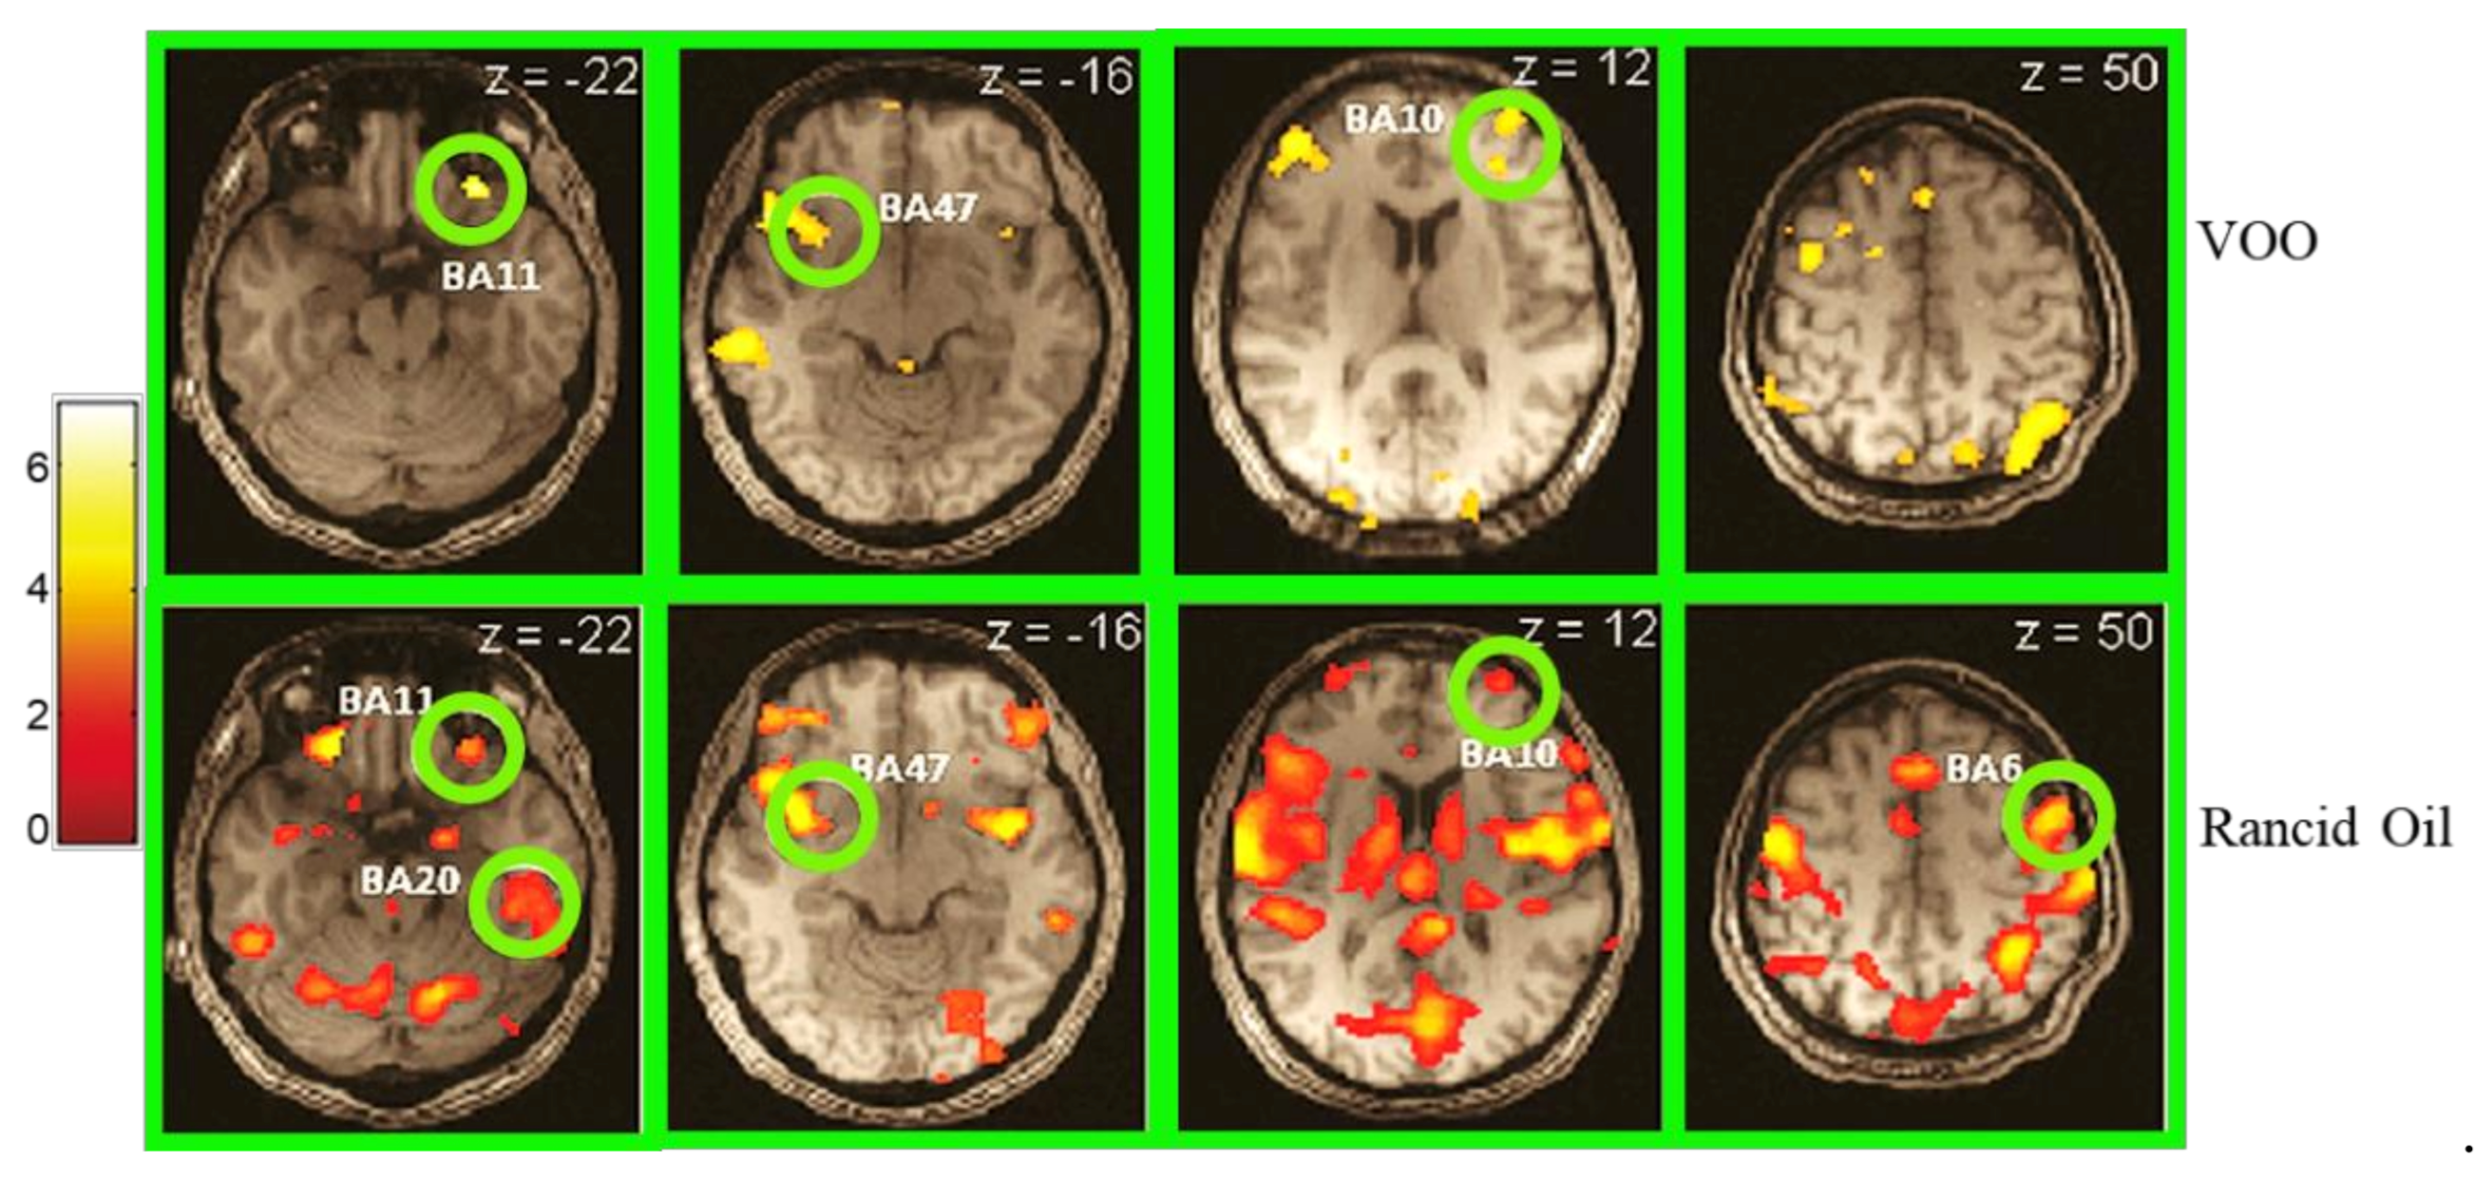

- García-González, D.L.; Vivancos, J.; Aparicio, R. Mapping Brain Activity Induced by Olfaction of Virgin Olive Oil Aroma. J. Agric. Food Chem. 2011, 59, 10200–10210. [Google Scholar] [CrossRef]

- Frank, S.; Linder, K.; Fritsche, L.; Hege, M.A.; Kullmann, S.; Krzeminski, A.; Fritsche, A.; Schieberle, P.; Somoza, V.; Hinrichs, J.; et al. Olive oil aroma extract modulates cerebral blood flow in gustatory brain areas in humans. Am. J. Clin. Nutr. 2013, 98, 1360–1366. [Google Scholar] [CrossRef] [PubMed][Green Version]